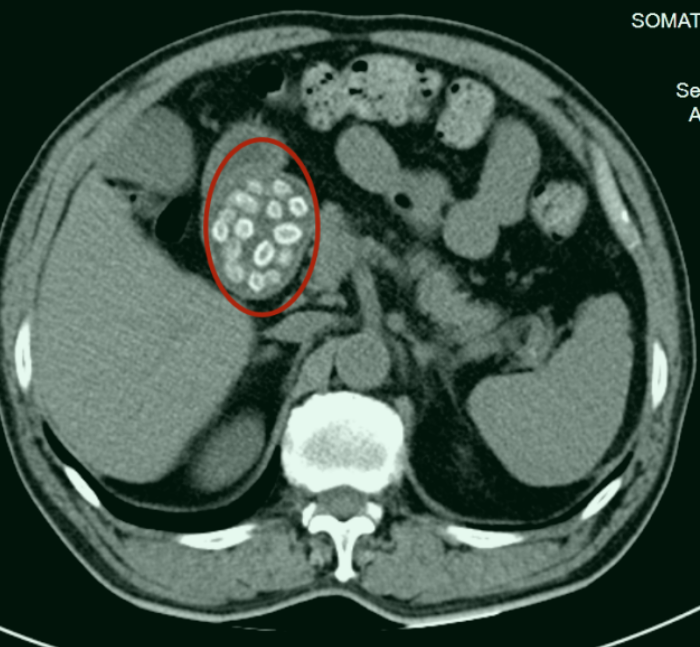

潘航海判断患者大概率是杨梅核导致梗阻。果然,CT检查发现,患者体内有杨梅核,密密麻麻,诊断为胃潴留、十二指肠梗阻。医生为大伯进行了紧急处理。

“胃镜检查发现患者胃腔内少量杨梅核,大量杨梅核与食物黏附,完全占据了十二指肠管腔,堵塞了十二指肠,胃镜无法通过……”潘航海描述当时的情景,十二指肠管腔较小,杨梅核形成的团块就像多层蛋糕一样叠在一起,后续治疗中,潘航海总共取了近60颗杨梅核,患者腹痛等症状明显缓解了,避免了外科手术。